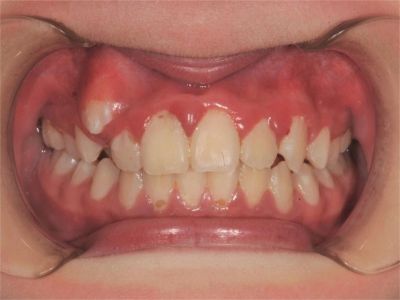

牙龈炎是发生于牙龈组织的炎症,患者可出现牙龈出血伴肿胀、发红、正常形态改变和偶尔不适等症状。本病主要由口腔卫生状况差导致,包括口腔不洁、牙菌斑等,诊断依据临床检查,治疗包括专业牙齿清洁和加强家庭口腔卫生。

牙龈炎可先引起牙齿与牙龈之间的沟(龈沟)加深,然后牙龈充血,炎症围绕一个或多个牙齿,伴牙龈乳头肿胀和易出血。一般无痛,可自行消退,也可维持轻度炎症数年。

牙龈炎常见的病因是口腔卫生差,不良的口腔卫生使牙菌斑沉积于牙齿与牙龈之间,造成龈沟加深,另外牙结石、不良修复体等也可造成牙龈炎的发生。